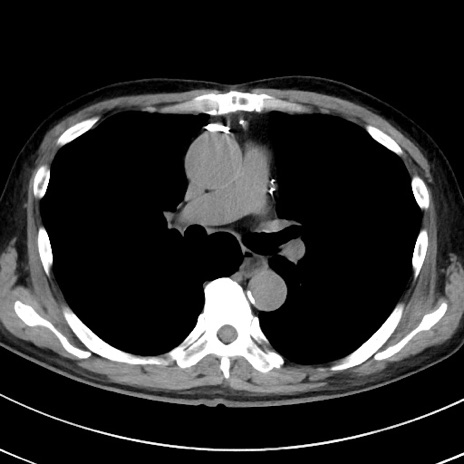

冠状断像